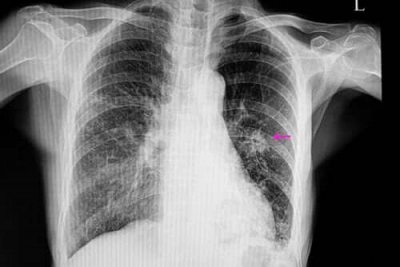

Nódulo Pulmonar Solitário

O Nódulo Pulmonar Solitário é uma lesão discreta. Ele tende a ser encontrado nos exames periódicos, como, por exemplo, em uma tomografia da região do tórax ou, até mesmo, em uma radiografia.